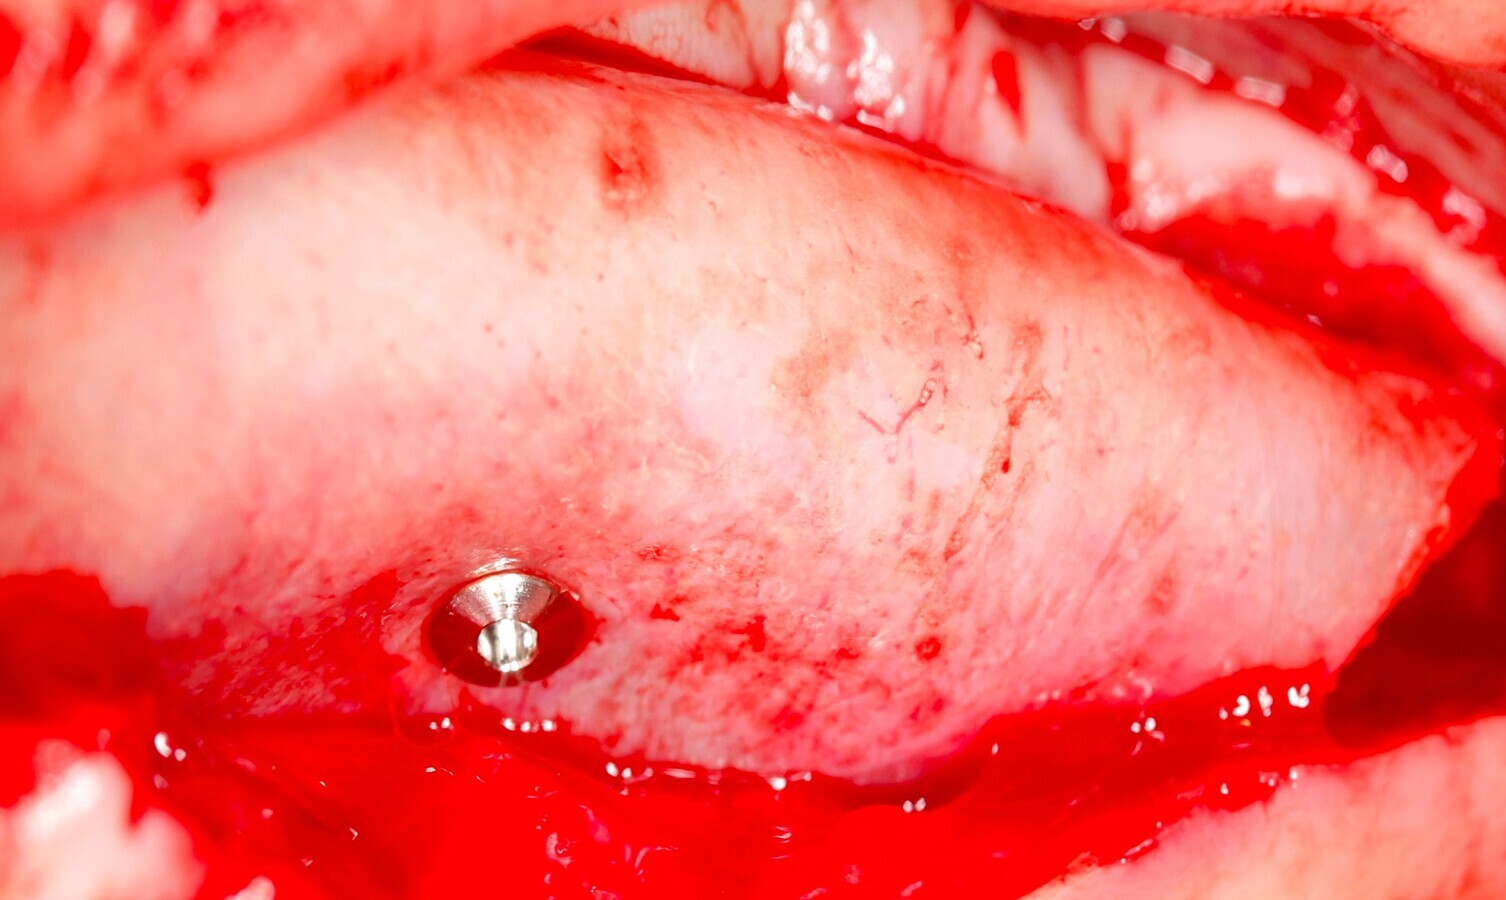

Fig. 12 Figura 12

1. Reposición del colgajo mucoperióstico, en el caso de la liberación del perióstico para garantizar un colgajo sin tensión, cierre primario del lecho10.

2. Sutura del colgajo con puntos simples y colchoneros horizontales con sutura 4/011,12.